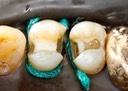

Joe Cha #20 pre-op